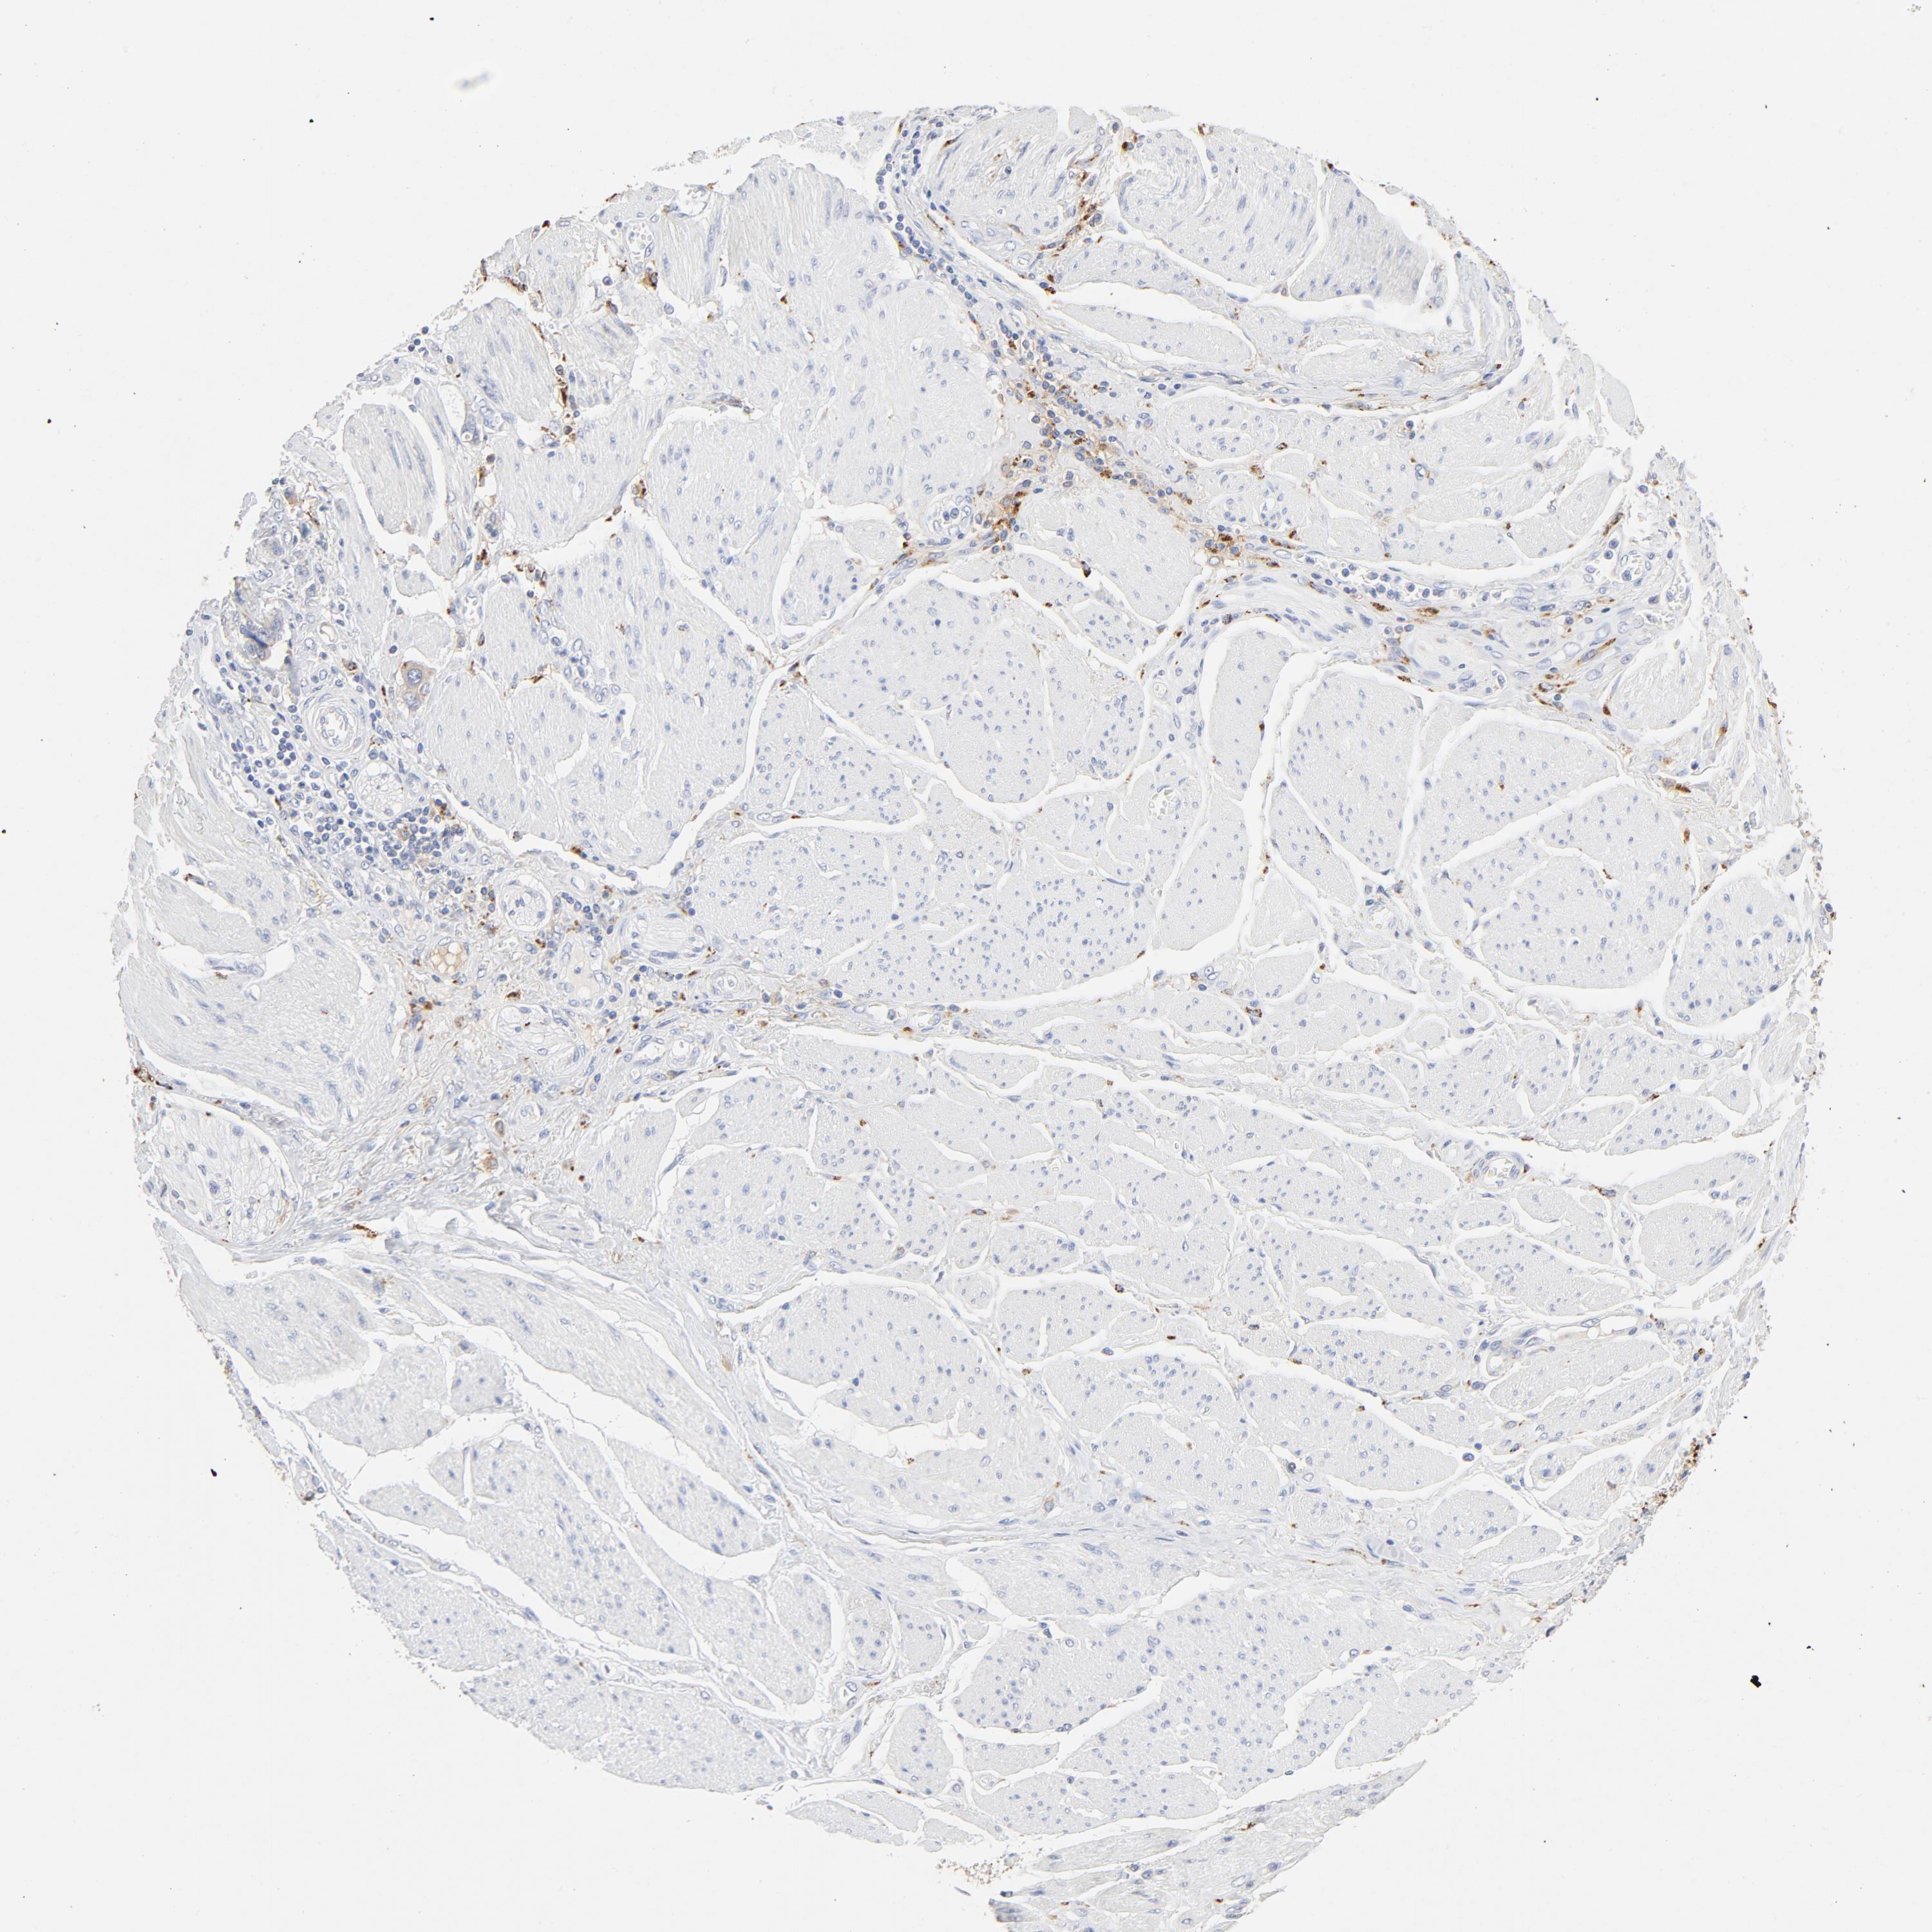

STOMACH CANCER - Protein expressioni

A mouse-over function shows sample information and annotation data. Click on an image to view it in a full screen mode. Samples can be filtered based on level of antibody staining by selecting one or several of the following categories: high, medium, low and not detected. The assay and annotation is described here.

Note that samples used for immunohistochemistry by the Human Protein Atlas do not correspond to samples in the TCGA dataset.

Antibody stainingi

Antibody staining in the annotated cell types in the current human tissue is reported as not detected, low, medium, or high, based on conventional immunohistochemistry profiling in selected tissues. This score is based on the combination of the staining intensity and fraction of stained cells.

Each image is clickable and will lead to virtual microscopy that enables deeper exploration of all samples and also displays staining intensity scores, fraction scores and subcellular localization as well as patient and tissue information for each sample.

Antibody HPA003756

Staining

High

Medium

Low

Not detected

Intensity

Strong

Moderate

Weak

Negative

Quantity

>75%

75%-25%

<25%

None

Location

Nuclear

Cytoplasmic/membranous

Cytoplasmic/membranous,nuclear

Adenocarcinoma, NOS